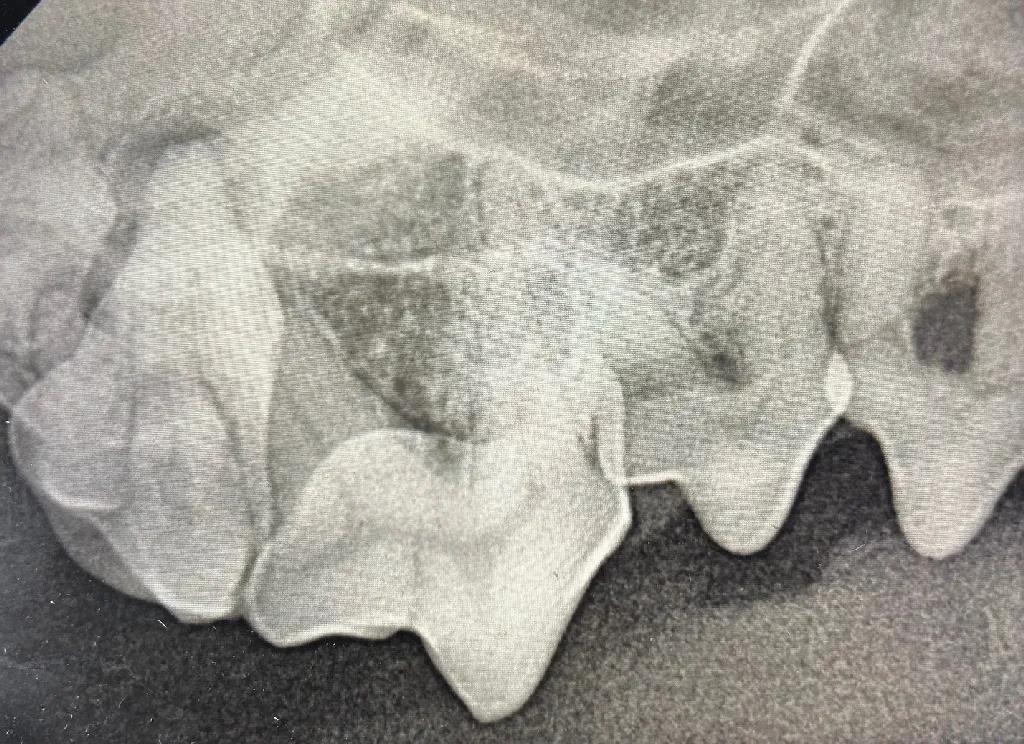

At Meadowmont Animal Hospital, we employ advanced digital radiology technology to swiftly and accurately diagnose your pet’s medical conditions. Digital radiology allows us to obtain detailed, high-resolution images of your pet’s internal structures quickly, minimizing stress and discomfort. These services are available for pets, ensuring comprehensive care for all species.

- Enhanced ability to diagnose fractures, internal abnormalities, and dental conditions